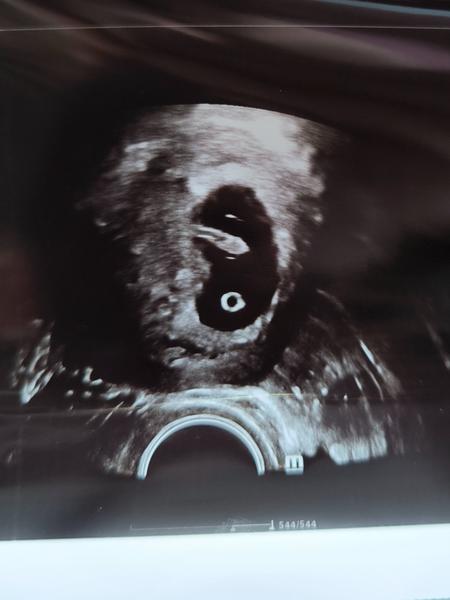

Sono v 8. týždni

Ahojte, včera som bola na sone, doktorka mi povedala že ie všetko ok, len ma zaujíma keď som si doma pozerala fotku, že čo to je za zhluk buniek naľavo pod embryom na tej fotke. Môze to byť vyvíjajúca sa placenta? Ak je tu niekto kto sa v tom vyzná, že by mi povedal čo to je.

@nikus_259 to je zltkovy vak a on sa neskôr zmení na placentu

@natalis1998 áno, tá gulička dole je žĺtkový vak, ale naľavo nad tou guličkou je čo? Myslím ako y na stene toho gestačn3ho valu, pod embryom

Žĺtkovy vačok,z neho sa vyvinie placenta.